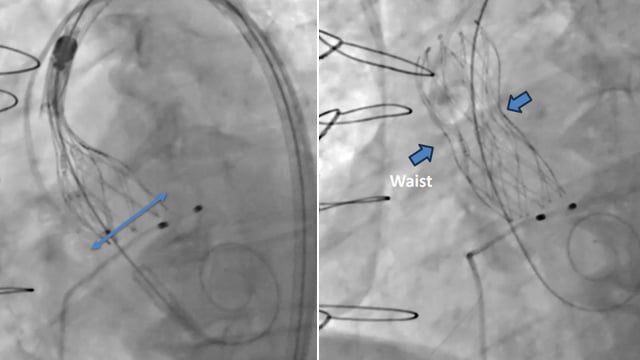

Left atrial appendage occlusion

17 Nov 2025 – From PCR London Valves 2025

This session focuses on the complexities and innovations in left atrial appendage occlusion (LAAO) procedures. It covers transesophageal ICE monitoring, challenges posed by existing atrial septal occluders, combined surgical and percutaneous approaches, and the practical experience with the Ultraseal device. These insights advance understanding of procedural...